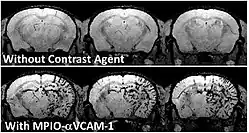

Molecular MRI of a mouse brain presenting acute inflammation in the right hemisphere. Whereas unenhanced MRI failed to reveal any difference between right en left hemispheres, injection of a contrast-agent targeted to inflamed vessels allows to reveal inflammation specifically in the right hemisphere.

To achieve molecular imaging of disease biomarkers using MRI, targeted MRI contrast agents with high specificity and high relaxivity (sensitivity) are required. To date, many studies have been devoted to developing targeted-MRI contrast agents to achieve molecular imaging by MRI. Commonly, peptides, antibodies, or small ligands, and small protein domains, such as HER-2 affibodies, have been applied to achieve targeting. To enhance the sensitivity of the contrast agents, these targeting moieties are usually linked to high payload MRI contrast agents or MRI contrast agents with high relaxivities.[2] In particular, the recent development of micron-sized particles of iron oxide (MPIO) allowed to reach unprecedented levels of sensitivity to detect proteins expressed by arteries and veins.[3]